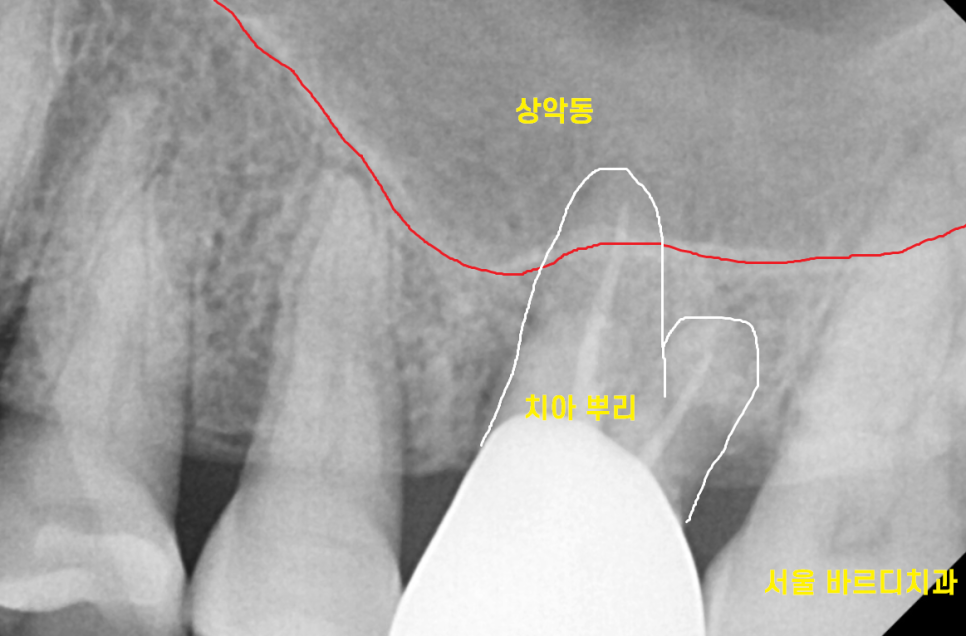

임플란트를 위해 ct 촬영을 시행했습니다.

치아 뿌리 끝과 상악동 구조물이 너무 가깝네요.

지난 시간에 임플란트를 심기 위해서는

최소 810mm 길이가 필요하다고 말씀드렸죠?

부족한 길이만큼 상악동을 들어 올려

뼈 이식 후 임플란트를 해야겠네요.

진단 결과 남아있는 뼈의 두께도 얇고

치아 뼈 폭도 좁아서 Lateral 방법으로 진행하기로 상담 드렸습니다.